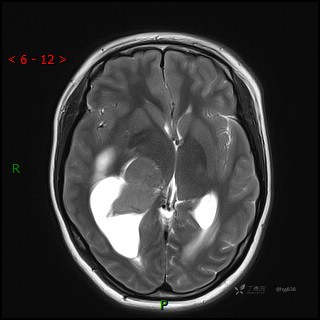

MRI平扫

CE